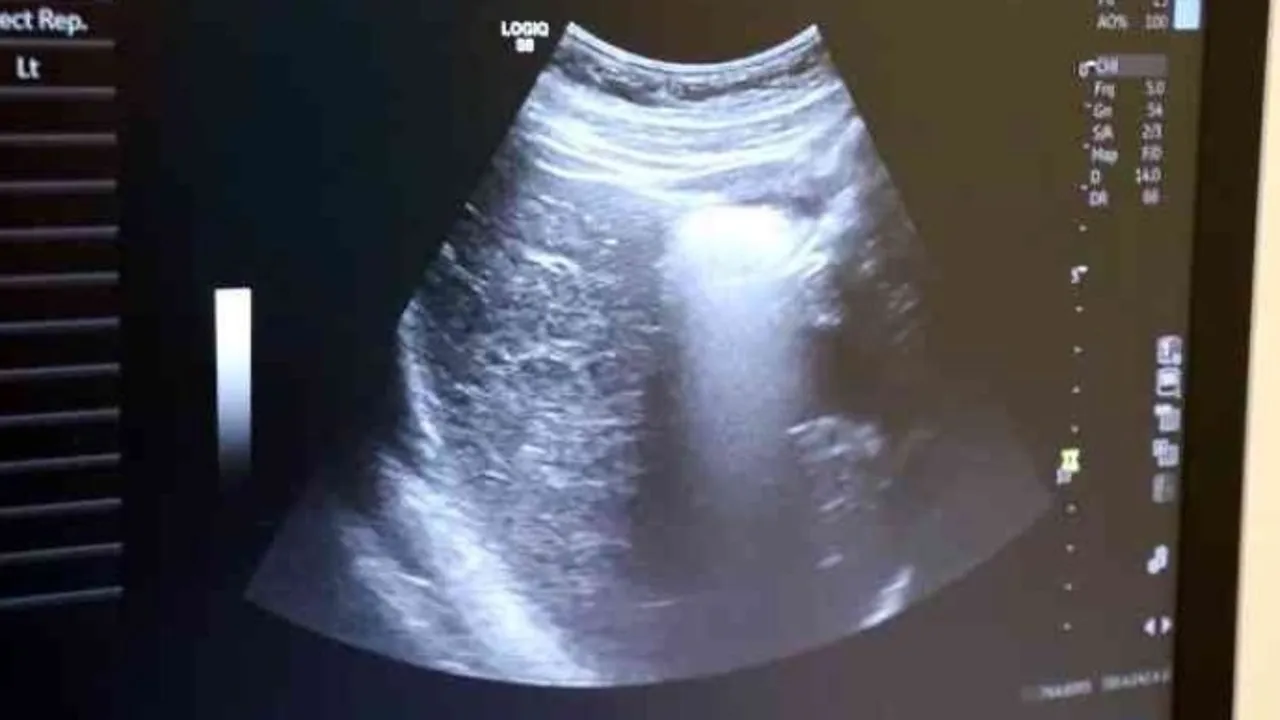

Ayrıntılı ve 4 boyutlu ultrason ile bebeklerin doğmadan önceki sağlık durumlarının belirlenebileceğine değinen Uzm. Dr. İlker Eroğlu, “Ultrason; yüksek frekanslı ses dalgalarının bilgisayar işlemcisinde işlenip, kablo arayıcılığıyla monitöre aktarılmasıdır. Son yıllarda gebelikte ayrıntılı ultrason gerekliliği giderek artmaktadır. Yaklaşık 50 yıl önce ultrason yaygın değilken doğumlarda bebek nasıl doğacak, sağlıklı mı sağlıksız mı doğacak ya da cinsiyet bile bilinemiyordu. 4 boyutlu ultrasonda ya da ayrıntılı ultrasondan sonra bebeğin sakatlıkları doğumdan önce anlaşılıp, tedavisi mümkün olanlar da doğumdan önce tedavi edilebilir oldu. Böylelikle bebeklerin daha sağlıklı olarak dünyaya gelmesi sağlanmış oldu. O nedenle ayrıntılı ultrason gereklidir” dedi.

Renkli ultrasonlarda bebeklerin anne karnındayken sakatlığı olup olmadığının belirlendiğini ifade eden İlker Eroğlu, “4 boyutlu ultrason halk arasında ‘renkli ultrason' diye bilinir. Anneler bu ultrasonda bebeğin görüntüsünü anladığı için onu daha çok sever. Hekimler genelde ultrasona siyah-beyaz bakar. 4 boyutlu ultrason iç organlar hakkında detaylı bilgi vermez. Biz detaylı ultrasonda (2. düzey ultrason) bebeğin iç organlarına yönelik incelemeyi siyah beyaz olarak yaparız. O nedenle bizim için siyah-beyaz ve 2 boyutlu olarak yapılan inceleme daha önemlidir. 4 boyutlu ultrasonda da faydalandığımız yerler vardır. 4 boyutlu ultrasonda örneğin; bebeğin kolu-bacağı yoksa, dudak yarığı varsa, gösterebiliriz. Çeşitli anatomik deformasyonları da anneye gösterebiliriz. Hala dünyada ayrıntılı ultrason 2 boyutlu ve siyah-beyaz olarak yapılır” diye konuştu.